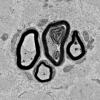

3B1B Case 3 GBS Nerve Bx_025 - Copy

3B1C Case 3 GBS Nerve Bx_026 - Copy

3B2 (Case 3) 023 - Copy copy

3B2 AIN_058 - Copy

3B2 AMPK KO Mouse Degen Axons_031.jpg

3B2 Axonal Degeneration (Case 4) EM 085 - Copy

3B2 Diabetes longitudinal, SLC (Case 3) 015 - Copy

3B2 Dmyel, remyel & AD (Case 3) EM 050 - Copy

3B2 Sarcoid (Case 3) Plastic 13A

3B2A GBS (Case 3) EM 034 - Copy

3B2A SLE Case 1)_013 - Copy

3B2B GBS (Case 3) EM 035 - Copy